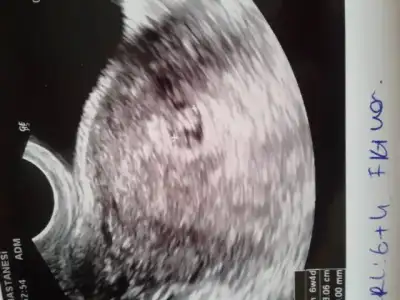

merhaba kızlar dün öğlen lekelenmem olduğu için dr a gıttık bebeğimin kalp atışlarını gördüm duydum o heyecanla eve geldik akşam 18:30 gibi lekelenmem olduğunu gördüm 5 dk sonra kanama başladı oğlum olduğu için hemen gdemedim hastaneye eşimde 1.5 saatlık yola gitmişti annemi aradım geldi beraber gıttık ben kürtaj olurum düşüncesiyle içeri girdim muayene olurken oda neeeeee kuzum hala benimlee inanamadımm dr da şaşırdı çünkü kan geldi yani sonrası siyah kahverengi lekelerr sata göre 7+3 bebeğe göre 6+4 idik dun bugun 6+5 olduk ama kesemiz ufak o canımı sıktı riskli bir gebelik dedi iğne vurdular eve geldim ama suanda k. rengi ve siyah lekelenme hala devam ediyor kesemizin ufak olması canımı sıkıyor çünkü bebeğin alanı daralıyor kese büyümezse muhtemelen kuzumu kaybedicem ama dr bu şeklide başlayıp sağlıklı olan gebelikler var suanda bişey diyemem dedi buda kuzummm